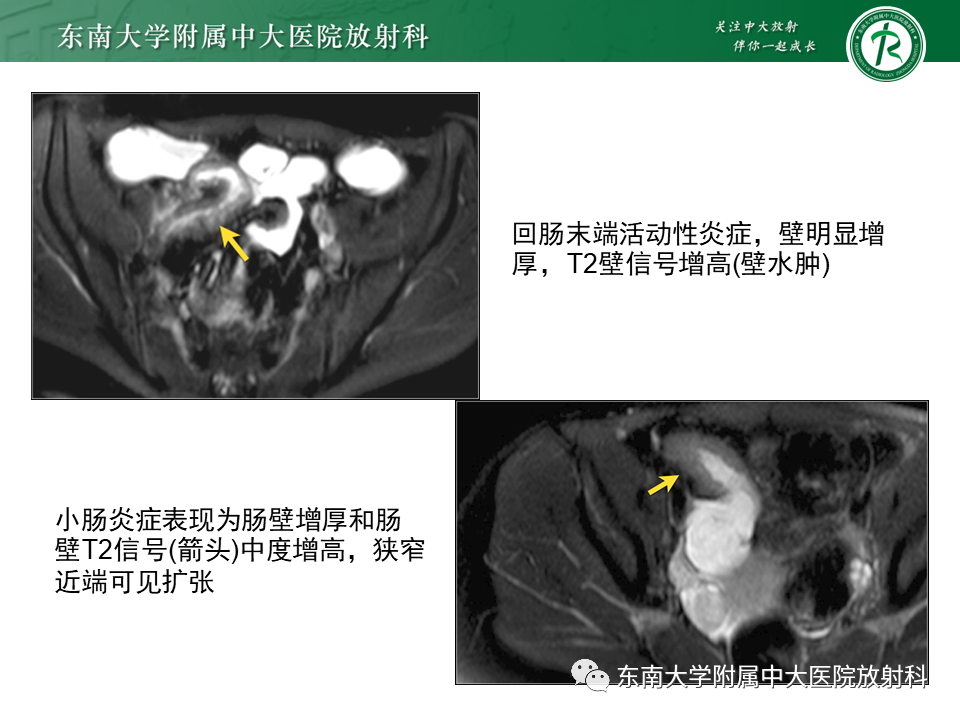

克罗恩病